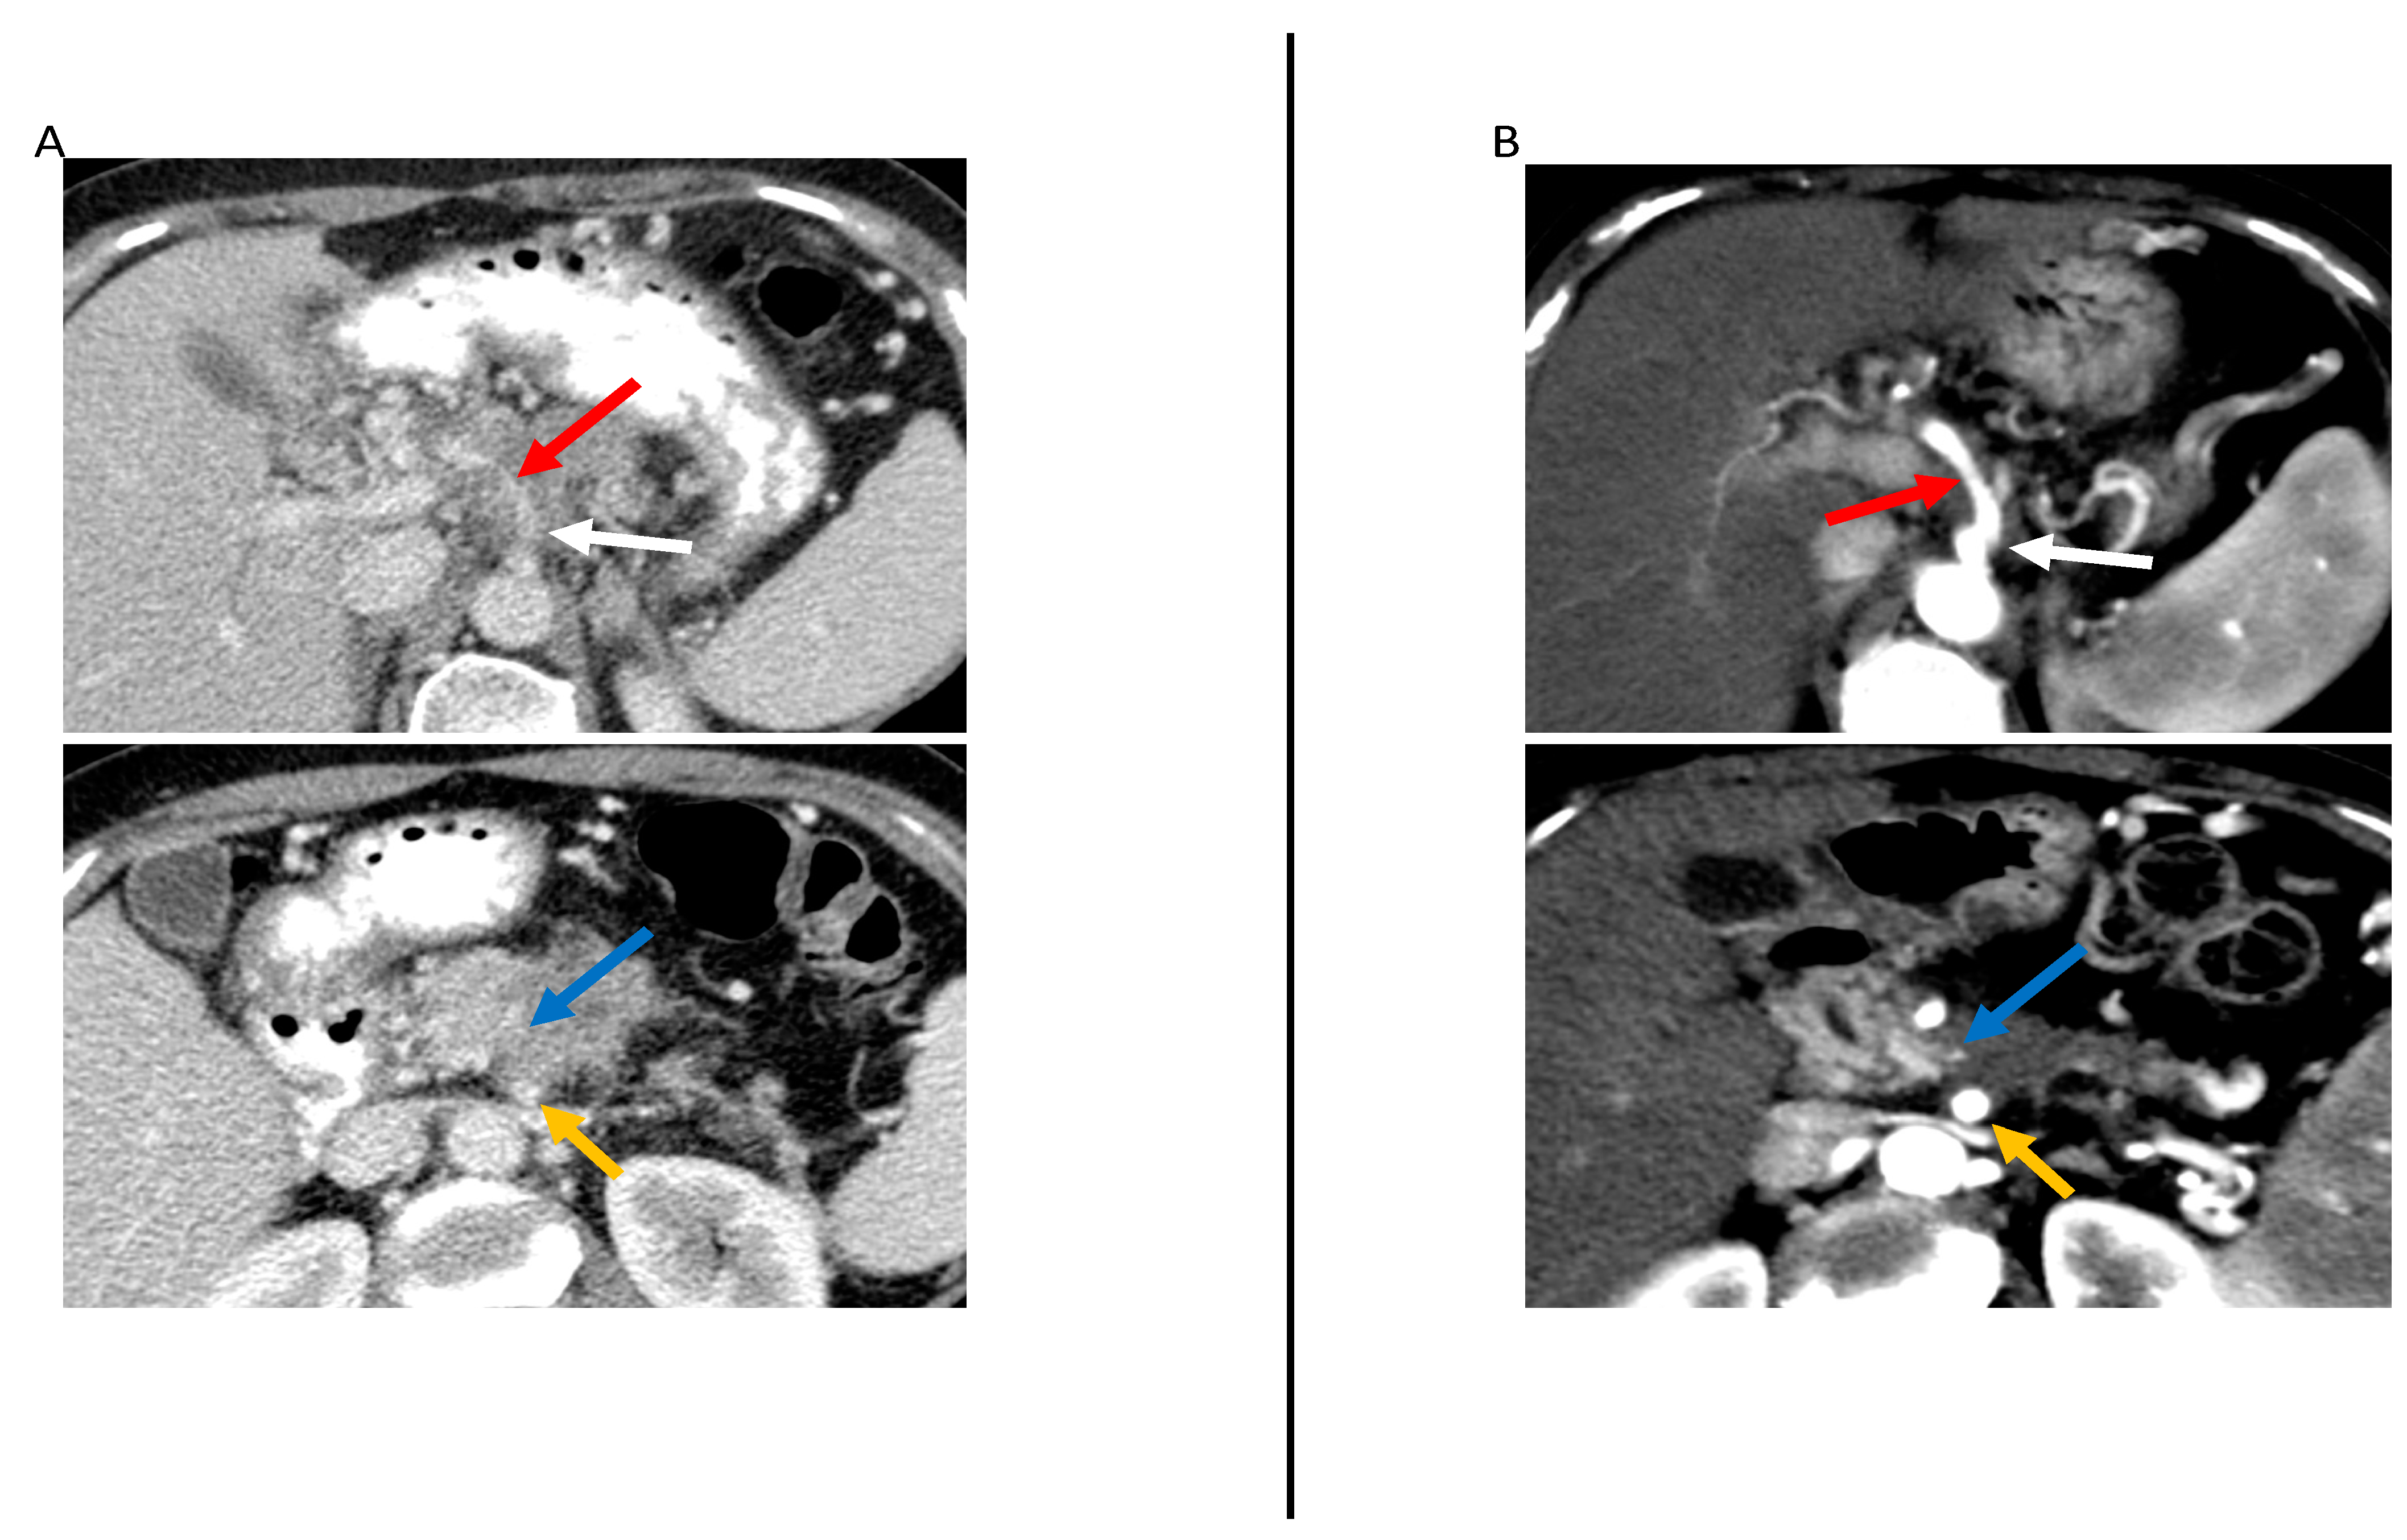

Figure 4.

59-year-old woman with locally advanced pancreatic cancer before and after neoadjuvant therapy. Contrast-enhanced CT in the axial plane at primary staging (A) and restaging after neoadjuvant therapy (B) demonstrate an ill-defined pancreatic neck and body tumor (with markedly decreased size after neoadjuvant therapy (blue arrow). At primary staging, the tumor was abutting the celiac artery (white arrow) superior mesenteric artery (SMA) (yellow arrow), causing vessel irregularity and narrowing (red arrow). After neoadjuvant therapy, the SMA abutment by the tumor was overall unchanged, although the artery irregularity and narrowing resolved. Additionally, the soft tissue surrounding the SMA had an enhancement < 30 HU. The patient underwent surgical resection after neoadjuvant therapy and there was no evidence of arterial involvement.

Regarding tumor attenuation, Marchegiani et al. [36] found that increased tumor attenuation in the arterial and venous phases after neoadjuvant therapy was associated with R0 resection in patients with locally advanced and borderline resectable tumors (p < 0.001 and p = 0.001, respectively). However, in Cassinotto et al. [33] and Wagner et al. [34], attenuation was not associated with R0 resection.

Regarding vascular contact/involvement, Cassinotto et al. [33] demonstrated that partial regression of tumor–vessel contact after neoadjuvant therapy had 100% positive predictive value for R0 resection, regardless of the degree of either reduction in tumor size or residual vascular involvement (Figure 4). Otherwise, studies showed that vascular contact/involvement was not associated with R0 resection [34,40].

Low contrast enhancement of the soft tissue contacting the artery (≤46.4 HU) was shown by Jang et al. [40] to be associated with R0 resection (adjusted odds ratio = 7.4; p = 0.01). Jang et al. also found that regression or stability of the NCCN resectability status after neoadjuvant therapy was associated with improved recurrence-free survival (Figure 4).